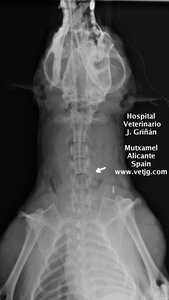

radiografía: imagen del postoperatorio, indicando la zona abordada |

A los 15 dias de la cirugia |